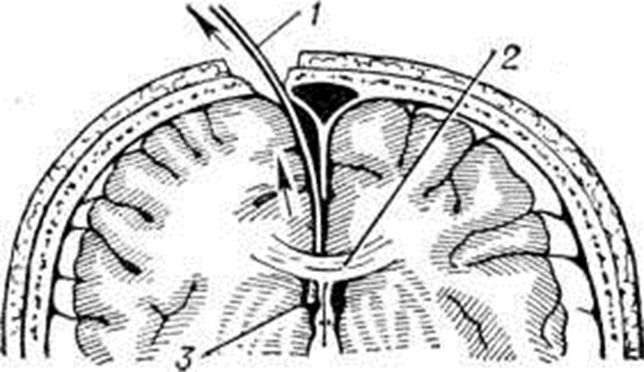

ГидроцефалияГидроцефалия (hydrocephalus; греческий hydor вода + kephale голова; синонимы водянка головного мозга) — состояние, характеризующееся избыточным накоплением цереброспинальной жидкости в желудочках мозга и подоболочечных пространствах. Гидроцефалия является следствием различных заболеваний или травм головного мозга и его оболочек. КлассификацияНаибольшее распространение в СССР получила классификация, предложенная А. А. Арендтом в 1948 год. В ней Гидроцефалия рассматривается в зависимости от времени возникновения, течения, этиологического факторов, локализации и характера нарушения функции ликворного аппарата. По времени возникновения различают врождённую и приобретённую Гидроцефалия, по течению — острую и хроническую. По локализации выделяют наружную и внутреннюю Гидроцефалия При наружной Гидроцефалия имеется избыточное скопление цереброспинальной жидкости преимущественно в субарахноидальных пространствах, при внутренней — в желудочках головного мозга. Нередко наблюдается комбинация внутренней и наружной Гидроцефалия — так называемый общая Гидроцефалия По характеру нарушения функции ликворного аппарата принято различать открытую (сообщающуюся) и закрытую (окклюзионную) Гидроцефалия Открытую Гидроцефалия в свою очередь подразделяют на гиперсекреторную, при которой секреция цереброспинальной жидкости значительно повышена, и арезорбтивную, характеризующуюся нарушением её всасывания. При окклюзионной Гидроцефалия имеется нарушение на различных уровнях оттока цереброспинальной жидкости из желудочков в субарахноидальные пространства в результате спаечного процесса, кист, опухолей и так далее. Встречаются смешанные формы Гидроцефалия, когда окклюзия ликворных путей сочетается с нарушением резорбции или секреции цереброспинальной жидкости. Этиология и патогенезРазличные поражения головного мозга и его оболочек могут привести к Гидроцефалия Чаще всего она наблюдается после инфекционных заболеваний (гнойный эпидемический цереброспинальный менингит, вторичные менингиты и менингоэнцефалиты) и черепно-мозговых травм. Кроме того, Гидроцефалия может возникнуть при затруднении оттока крови из полости черепа (патология венозной системы, тромбоз синусов, сдавление рубцами и спайками отводящих вен), при опухолях, а также при гипертензии, заболеваниях почек и паразитарных поражениях головного мозга. Иногда Гидроцефалия возникает в результате аномалии развития головного и спинного мозга (недоразвитие мозга, мозговые и спинномозговые грыжи и так далее). Вышеперечисленные причины могут привести к нарушению секреции, всасывания или циркуляции цереброспинальной жидкости с последующим развитием Гидроцефалия Патологическая анатомияМорфологически изменения в мозге и оболочках при Гидроцефалия зависят как от основного заболевания, приведшего к Гидроцефалия, так и от длительности повышенного внутричерепного давления. Как правило, наблюдается расширение полостей желудочков, особенно боковых, за счёт увеличения в них количества цереброспинальной жидкости (рисунок 1). Боковые желудочки расширены симметрично как при открытой, так и закрытой Гидроцефалия с окклюзией межжелудочковых отверстий водопровода мозга и апертур IV желудочка (рисунок 2—4). |

Асимметричное расширение желудочков чаще всего наблюдается при закупорке одного межжелудочкового отверстия или на стороне травмы. Прогрессирующее увеличение желудочков приводит к атрофии мозговой ткани, уплощению извилин и сглаживанию борозд мозга. Рано поражаются пирамидные пути. Изменению подвергается прежде всего белое вещество, мозолистое тело и свод. Изменение серого вещества наблюдается при Гидроцефалия в результате травмы и в тяжёлых случаях Гидроцефалия. При врождённой Гидроцефалия может нарушаться строение коры. Атрофия нервной ткани при Гидроцефалия, по мнению У. Пенфилда и Элвиджа (A. Elwidge, 1932), Б. Н. Клосовского (1949), В. П. Пурина (1968), происходит в результате сдавления капилляров мозга вследствие внутричерепной гипертензии. Выраженная астроцитарная реакция в белом веществе при Гидроцефалия является плохим прогностическим признаком. Кроме изменений со стороны ткани мозга, при Гидроцефалия отмечают выраженные изменения и со стороны сосудистых сплетений, эпендимы желудочков и его оболочек. Наблюдается атрофия сосудистых сплетений с фиброзным перерождением их соединительнотканной основы и гибелью эпителия. При Гидроцефалия после инфекционных заболеваний выявляют признаки гранулематозного эпендиматита (смотри Хориоэпендиматит). Мозговые оболочки резко утолщены, мутны, отёчны. Отмечают их фиброз, сращение главным образом в области базальных цистерн основания мозга, большого затылочного отверстия и апертур IV желудочка. В оболочках выявляют воспалительные инфильтраты. При травматической Гидроцефалия в мозге находят следы бывших кровоизлияний, рубцы в местах некрозов мозговой ткани, спайки в области путей оттока цереброспинальной жидкости и так далее. В сосудах головного мозга при Гидроцефалия обнаруживают признаки артериосклероза с гиалинозом сосудов.

Рисунок 1. | ||